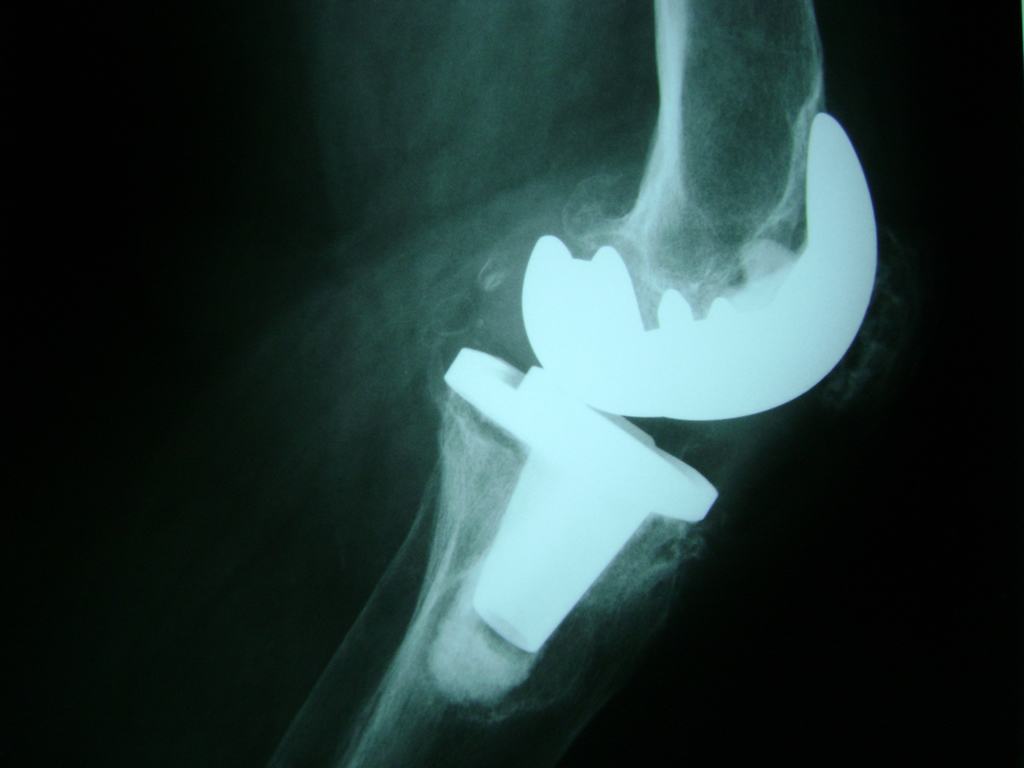

La artroscopia de rodilla es un cirugía en el cual la estructura interna de la articulación es examinada ya sea para realizar un diagnostico o para realizar un tratamiento, este procedimiento se realiza utilizando un instrumento parecido a un pequeño tubo llamado artroscopio.